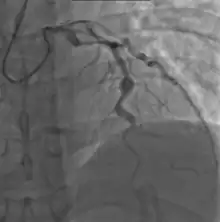

Heart complications are the most important aspect of Kawasaki disease, which is the leading cause of heart disease acquired in childhood in the United States and Japan.[31] In developed nations, it appears to have replaced acute rheumatic fever as the most common cause of acquired heart disease in children.[15] Coronary artery aneurysms occur as a sequela of the vasculitis in 20–25% of untreated children.[52] It is first detected at a mean of 10 days of illness and the peak frequency of coronary artery dilation or aneurysms occurs within four weeks of onset.[48] Aneurysms are classified into small (internal diameter of vessel wall <5 mm), medium (diameter ranging from 5–8 mm), and giant (diameter > 8 mm).[31] Saccular and fusiform aneurysms usually develop between 18 and 25 days after the onset of illness.[15]

Even when treated with high-dose IVIG regimens within the first 10 days of illness, 5% of children with Kawasaki disease develop at the least transient coronary artery dilation and 1% develop giant aneurysms.[53][54][55] Death can occur either due to myocardial infarction secondary to blood clot formation in a coronary artery aneurysm or to rupture of a large coronary artery aneurysm. Death is most common two to 12 weeks after the onset of illness.[15]

- Angiography was historically used to detect coronary artery aneurysms, and remains the gold standard for their detection, but is rarely used today unless coronary artery aneurysms have already been detected by echocardiography.